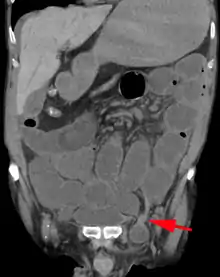

Medical imaging

A physician may diagnose an inguinal hernia, as well as the type, from medical history and physical examination.[20] For confirmation or in uncertain cases, medical ultrasonography is the first choice of imaging, because it can both detect the hernia and evaluate its changes with for example pressure, standing and Valsalva maneuver.[21]

When assessed by ultrasound or cross sectional imaging with CT or MRI, the major differential in diagnosing indirect inguinal hernias is differentiation from spermatic cord lipomas, as both can contain only fat and extend along the inguinal canal into the scrotum.[22]

On axial CT, lipomas originate posterolateral to the cord, and are located inside the cremaster muscle, while inguinal hernias lie anteromedial to the cord and are not intramuscular. Large lipomas may appear nearly indistinguishable as the fat engulfs anatomic boundaries, but they do not change position with coughing or straining.[22]